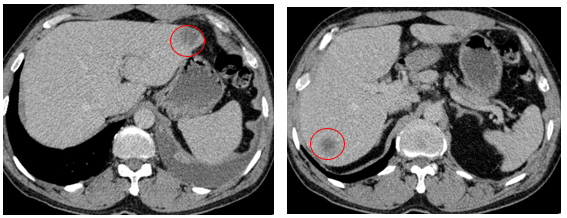

- Chụp cắt lớp vi tính ổ bụng (08/2025): Nhu mô gan phải có vài nốt, nốt lớn nhất hạ phân thùy VII có nốt giảm tỷ trọng, ngấm thuốc kém sau tiêm đường kính 24mm, hạ phân thùy II, III có nốt 2 giảm tỷ trọng đường kính 13mm và 27mm. Các ổ đặc xương rải rác đốt sống ngực thắt lưng, xương cùng và xương chậu hai bên – theo dõi tổn thương thứ phát

Hình 04: Nhu mô gan phải có vài nốt, nốt lớn nhất hạ phân thùy VII có nốt giảm tỷ trọng, ngấm thuốc kém sau tiêm đường kính 24mm, hạ phân thùy II, III có nốt 2 giảm tỷ trọng đường kính 13mm và 27mm

Hình 05: Các ổ đặc xương rải rác đốt sống ngực thắt lưng, xương cùng và xương chậu hai bên – theo dõi tổn thương thứ phát